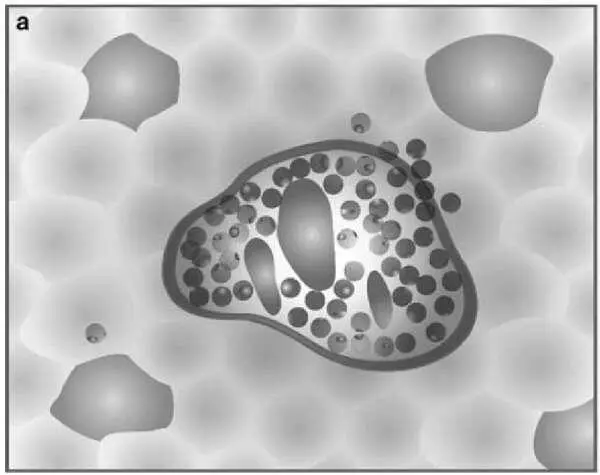

Разработчики ставили цель упростить шкалу. Оригинальность подхода заключается в том, что шкала представлена в виде 4 диаграмм, оценивающих некротические и воспалительные изменения в биоптате печени, и 4 диаграмм, оценивающих стадию фиброза .

Рисунок 5 – Схемы некротических и воспалительных изменений в печени (по Batts KP, Ludwig J.)

На рисунке представлена последовательная схема некротических и воспалительных изменений в печени при хроническом гепатите (по Batts–Ludwig). Воспалительная инфильтрация портальных трактов является обязательным компонентом поражения печени при гепатите и оценивается во всех системах. В оценочной шкале Баттс–Людвига выраженность гистологической активности гепатита градируется от 1 до 3 (a, b, c). На рисунке d представлена схема сливных некрозов в виде мостовидных некрозов, которые свидетельствуют о выраженной степени активности гепатита и соответствуют 4 стадии активности по системе Баттс–Людвига (Batts KP, Ludwig J. Chronic hepatitis. An update on terminology and reporting. Am J Surg Pathol 1995;19:1409–1417.15).